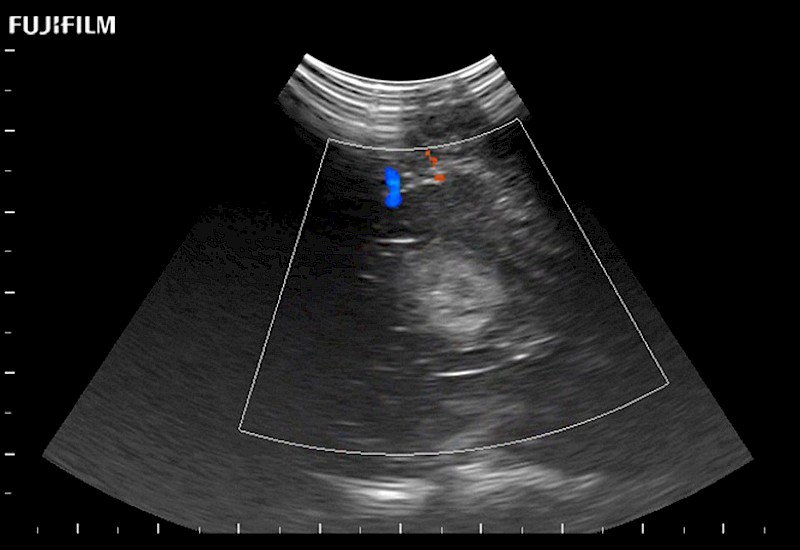

Extraordinary high-resolution digital imaging

Exceptional transducers

Multi-Parametric imaging modalities